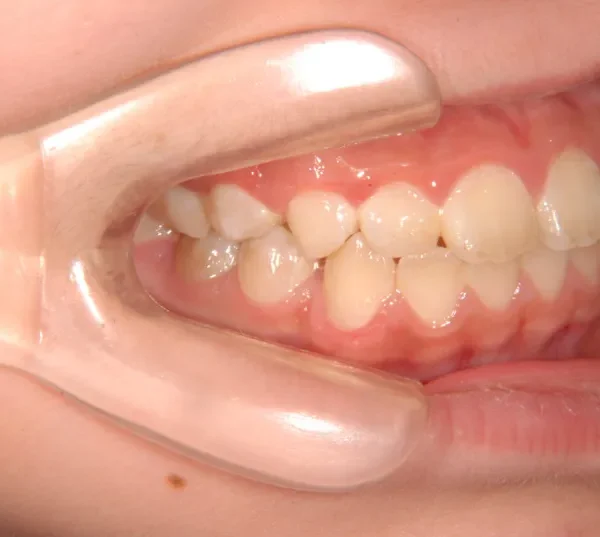

【子供の矯正(一期)】叢生・反対咬合・受け口・非抜歯症例・7歳女児【M.H様】

初診時年齢 小学校1年生 (女性) 主訴 受け口

診断名 叢生・反対咬合 装置名

状態 永久歯が生える隙間がない(叢生)

受け口(下顎前突/反対咬合)

下顎が大きい傾向があります。

上下の真ん中にズレがあるのと、上下とも永久歯の生えるスペースがせまいため、オリジナル矯正装置でスペースを作り、受け口も改善していきます。

治療回数21回、2年7ヶ月の治療期間で矯正治療を終了しました。

主訴が改善され、ご満足頂きました。

初診

治療終了後